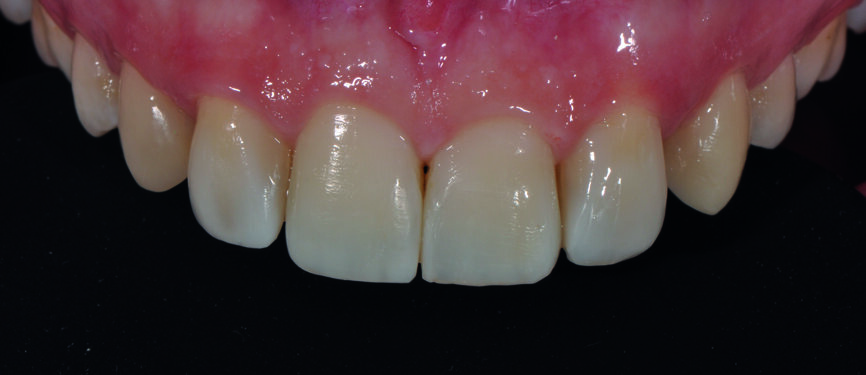

Fig. 6 : a) Gros plan du sourire après la fermeture du diastème avec le composite Essentia (GC).

Fig 6 b) : vue intraorale latérale.

Fig 6 c) : vue intraorale de face. La teinte du composite est bien intégrée, quelle que soit la direction d’où l’on regarde, indépendamment de la lumière incidente